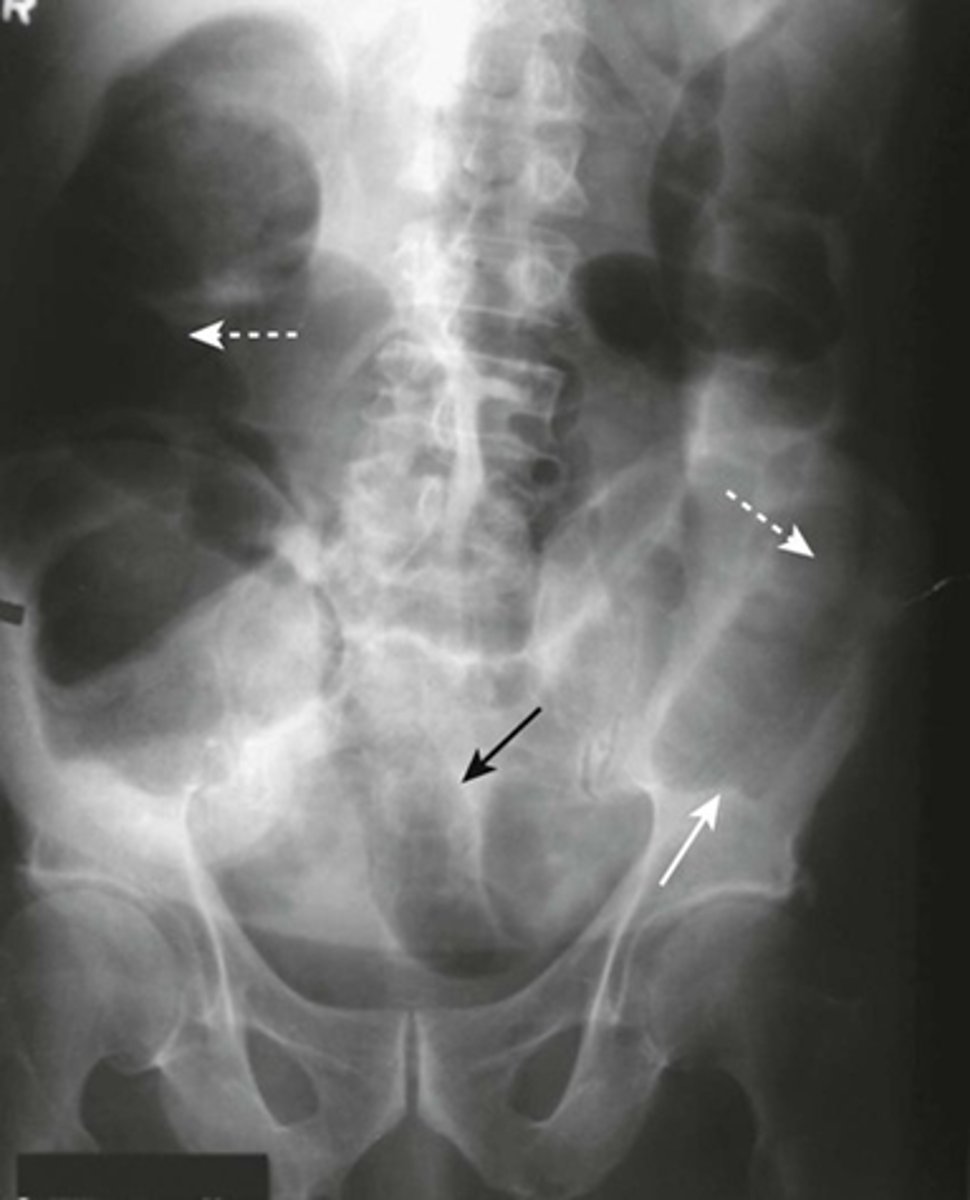

Partial SBO

SOLID BLACK ARROW (gas passing into colon)

DOTTED WHITE ARROW: small bowel is disproportionately dilated

SOLID WHITE ARROWS: Clips from prior surgery

A partial or incomplete mechanical SBO - allows some gas to pass the point of obstruction. Can be confusing as gas may pass into the colon and be visible long after the large bowel would be expected to be devoid of gas.

The important observation is that the small bowel is DISPROPORTIONATELY DILATED compared with the large bowel, a finding suggestive of SBO.

Partial or incomplete small bowel obstructions occur more often in patients in whom adhesions are the etiologic factors. Notice the clips (solid white arrows) attesting to prior surgery.